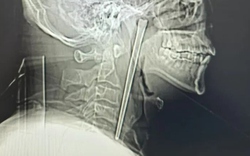

Người đàn ông đau họng dữ dội, bác sĩ lấy ra thứ đáng sợ bên trong

Sau khi kiểm tra, các bác sĩ vô cùng kinh ngạc khi phát hiện một chiếc đũa kim loại dài 12 cm bị mắc kẹt trong cổ họng của người đàn ông.